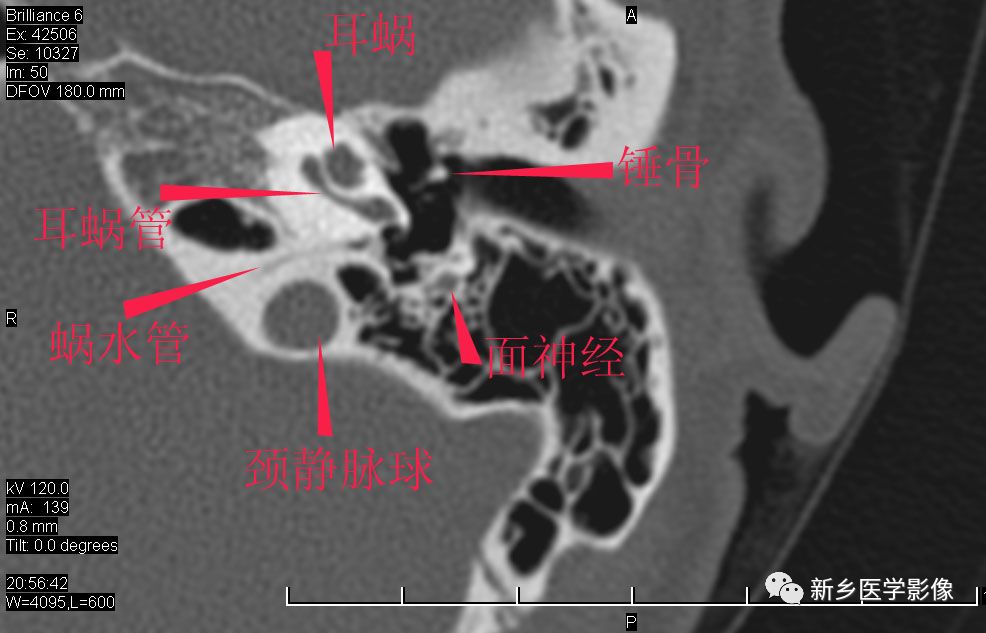

耳部详细解剖纯手工标注